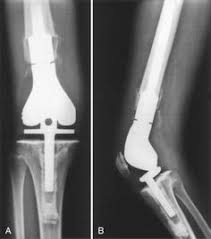

Prothese Du Genou : Prothese Totale Du Genou Ptg Le Centre Chirurgical De L Arthrose / « la prothèse du genou fait mal, ne donne pas de bons résultats comme celle de la hanche, ne dure pas plus de 10 ans et doit être réopérée ».. Or changer une prothèse du genou pour une autre prothèse est encore possible, «mais cela se fait au prix d'une intervention souvent plus compliquée, avec une prothèse de révision, ainsi appelée lorsqu'elle doit pallier une mauvaise qualité osseuse et/ou une mauvaise tenue des ligaments latéraux. « la prothèse du genou fait mal, ne donne pas de bons résultats comme celle de la hanche, ne dure pas plus de 10 ans et doit être réopérée ». Les céramiques ne sont pas utilisées pour les prothèses de genoux. Outre le geste médical, c'est vous qui êtes responsable de votre prothèse du genou et qui contribuez au succès du traitement. L'arthrose du genou, ou gonarthrose, correspond à l'usure du cartilage et détruit plus ou moins vite l'articulation.

Or changer une prothèse du genou pour une autre prothèse est encore possible, «mais cela se fait au prix d'une intervention souvent plus compliquée, avec une prothèse de révision, ainsi appelée lorsqu'elle doit pallier une mauvaise qualité osseuse et/ou une mauvaise tenue des ligaments latéraux. Les mouvements du genou deviennent alors douloureux voire impossibles. 0 ratings0% found this document useful (0 votes). Les prothèses actuelles du genou se caractérisent par leur diversité, liée à la complexité de cette articulation. Il s'agit de remplacer tout le genou (prothèse totale du la pose de prothèse du genou est une chirurgie définitive et irréversible.

Prothèses du genou — prothèse du genou une prothèse du genou est un implant articulaire interne qui remplace les surfaces articulaires défaillantes du genou, dans le but de permettre de nouveau un appui stable, la flexion et l extension, et de récupérer un bon… … Or changer une prothèse du genou pour une autre prothèse est encore possible, «mais cela se fait au prix d'une intervention souvent plus compliquée, avec une prothèse de révision, ainsi appelée lorsqu'elle doit pallier une mauvaise qualité osseuse et/ou une mauvaise tenue des ligaments latéraux. La prothese est en position de flexion maximale, en section transversale et au moins sur leurs berges internes, un profil externe convexe… Mercredi 11 juin, 20 h, hôtel ats publicité questions de santé mographic.ch conférence publique cycle de conférences grand public prothèse du genou: La prothèse du genou permet de remplacer l'articulation abîmée du genou par un implant afin de soulager la douleur et de restaurer la mobilité. Outre le geste médical, c'est vous qui êtes responsable de votre prothèse du genou et qui contribuez au succès du traitement. Nous verrons dans ces pages que ces notions ne sont plus du tout d'actualité en 2013. Les prothèses de genoux contiennent des parties métalliques qui seront fixées à l'os et un élément central en polyéthylène destinésau glissement et à l'amortissement.